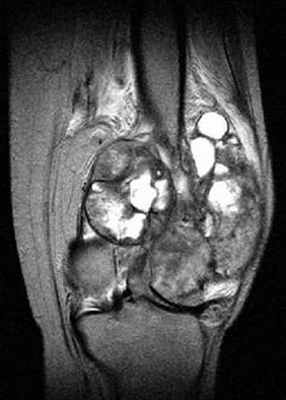

С помощью МРТ удается лучше оценить распространение опухоли внутри кости а также степень вовлечения внескелетных тканей (рис. 3).

Рис. 3. МРТ в диагностике и стадировании сарком костей.